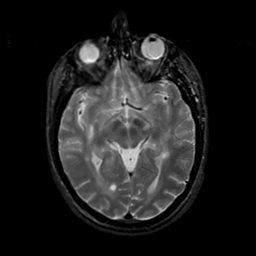

MR Study #18, July 21, 1991 -- Slice #22